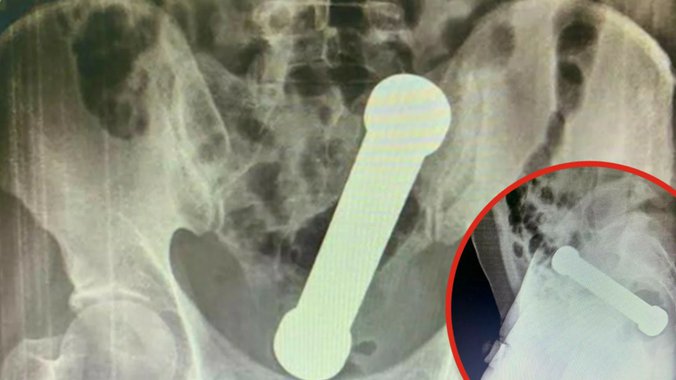

Na kraju su zahvaljujući rendgenskom snimku otkrili teg dugačak čitavih 20 centimetara koji se zaglavio na granici debelog creva i rektuma.